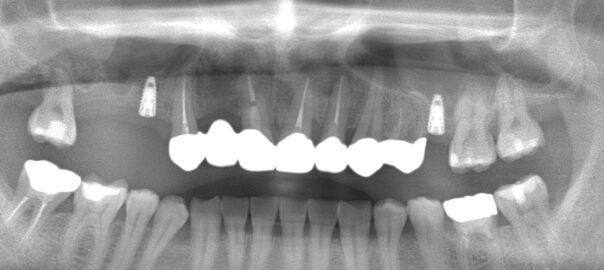

- 2023/12/07 どこまで残すか

こんにちは、静岡市駿河区にある歯科医院、小嶋デンタルクリニックです。 歯肉腫脹で来院された患者様のレントゲン。 小臼歯部に歯根破折を認め破折に沿って病巣を認めます。 … 続きを読む どこまで残すか

- 2023/11/29 上顎骨欠損

こんにちは、静岡市駿河区にある歯科医院、小嶋デンタルクリニックです。 インプラントのプランニング及び設計。 数本埋入を予定していますが、臼歯部にいけばいくほど骨が少なくなり骨造成 … 続きを読む 上顎骨欠損